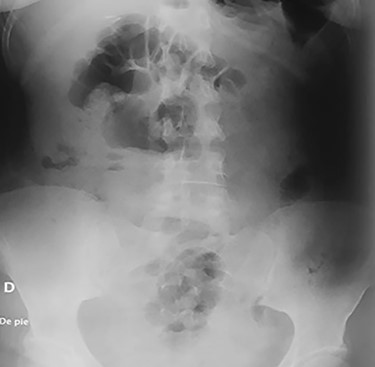

Her postoperative period was uneventful (Fig. 4); liquid diet was started on the second postoperative day and was followed by a full diet. A complete psychiatric evaluation was requested before discharge, and she was kept on close surveillance for a year. On follow-ups, the patient is doing well and is still under psychiatric surveillance and anti-depressive medication.

Abdominal X-ray on the postoperative period without any razor blades.